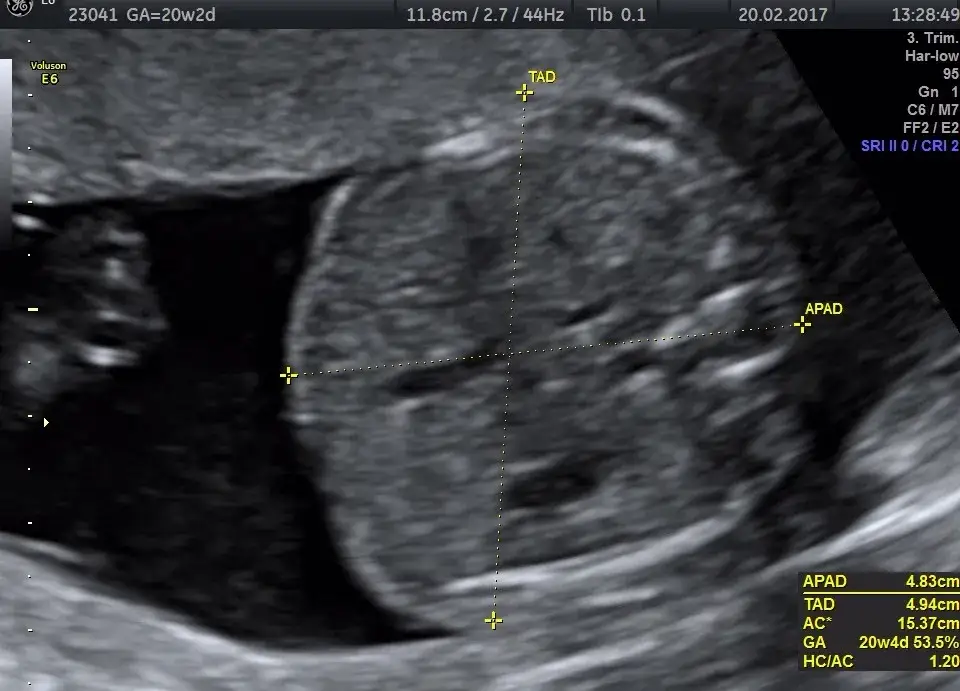

22. tydzień ciąży to idealny moment na wykonanie niezwykle ważnego badania USG połówkowego, zwanego również genetycznym USG II trymestru. Zazwyczaj przeprowadza się je między 18. a 22. tygodniem ciąży. To nie jest zwykłe USG; to szczegółowa ocena anatomii płodu, podczas której lekarz dokładnie sprawdza wszystkie narządy, mierzy poszczególne części ciała dziecka i ocenia jego rozwój, aby wykluczyć wady wrodzone.

Przygotowanie do USG połówkowego nie jest skomplikowane, ale warto pamiętać o kilku rzeczach. Przede wszystkim, postaraj się być zrelaksowana stres może wpływać na aktywność dziecka. Nie bój się zadawać pytań lekarzowi; to Twoja szansa, aby dowiedzieć się jak najwięcej o swoim maluszku i rozwiać wszelkie wątpliwości. To naprawdę magiczne doświadczenie, które pozwala zobaczyć Twoje dziecko w tak szczegółowy sposób!